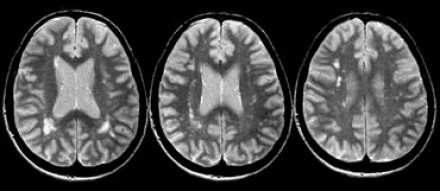

血管周圍間隙

圖片三:T2加權(quán)成像和FLAIR成像

請查看上圖并描述其病變特點。我們可以看到,在T2加權(quán)成像上,在基底節(jié)上有多個高密度病灶。在FLAIR成像上,這些病灶呈黑暗模糊影,在所有序列成像上,與腦脊液的密度相近(在T1加權(quán)成像上呈低信號)。

結(jié)合信號密度和病灶部位,可以判斷是典型的血管周圍間隙。

圖片四:FLAIR成像

血管周圍間隙是穿透軟腦膜血管周圍的腦脊液間隙。通常位于基底神經(jīng)節(jié)、腦室周圍、前連合附近以及腦干中間。在MR成像圖像上,在所有序列上的密度與腦脊液的密度相近。與其他白質(zhì)損傷病灶不同,血管周圍間隙在FLAIR和PD成像上呈黑暗模糊影,通常比較小,位于前連合附近的除外,此處的血管周圍間隙比較大。

在上圖中,我們可以看到比較寬的血管周圍間隙和在白質(zhì)中有融合的高密度信號病灶。該圖像很好的顯示了血管周圍間隙和白質(zhì)損傷病灶之間的差異。

由于周圍結(jié)構(gòu)組織的萎縮,血管周圍間隙會隨著衰老和高血壓而逐漸增寬。